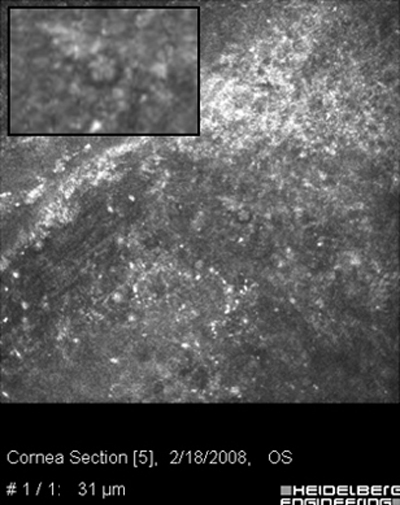

Ante la sospecha por los antecedentes e imágenes biomicroscópicas de una queratitis por Acantamoeba, debe hacerse su confirmación diagnóstica mediante extendidos de la superficie corneal para estudio microscópico, con las imágenes obtenidas “in vivo” con microscopía confocal (Figura 31 y 32) y mediante cultivos del parásito.

Fig. 31 Microscopía Confocal

Fig. 32 Comparar con quiste Acanthamoeba Fig 39

La positividad por la presencia de Acanthamoebas en uno o más estos estudios, asociada a las imágenes clínicas, confirma la etiología de la queratitis e indican la conducta terapéutica a seguir.